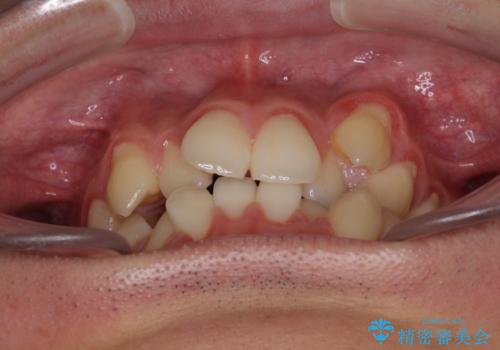

- 上下の八重歯や乱杭歯を気にして来院され患者様です。

スペースを確保するため、上下左右の小臼歯を抜歯し、ワイヤー装置に矯正することとしました。

奥歯の咬み合わせの左右差が大きかったため、変則的な抜歯矯正を行いました。

治療期間はやや長期化しましたが、満足のいく歯並びとなりました。